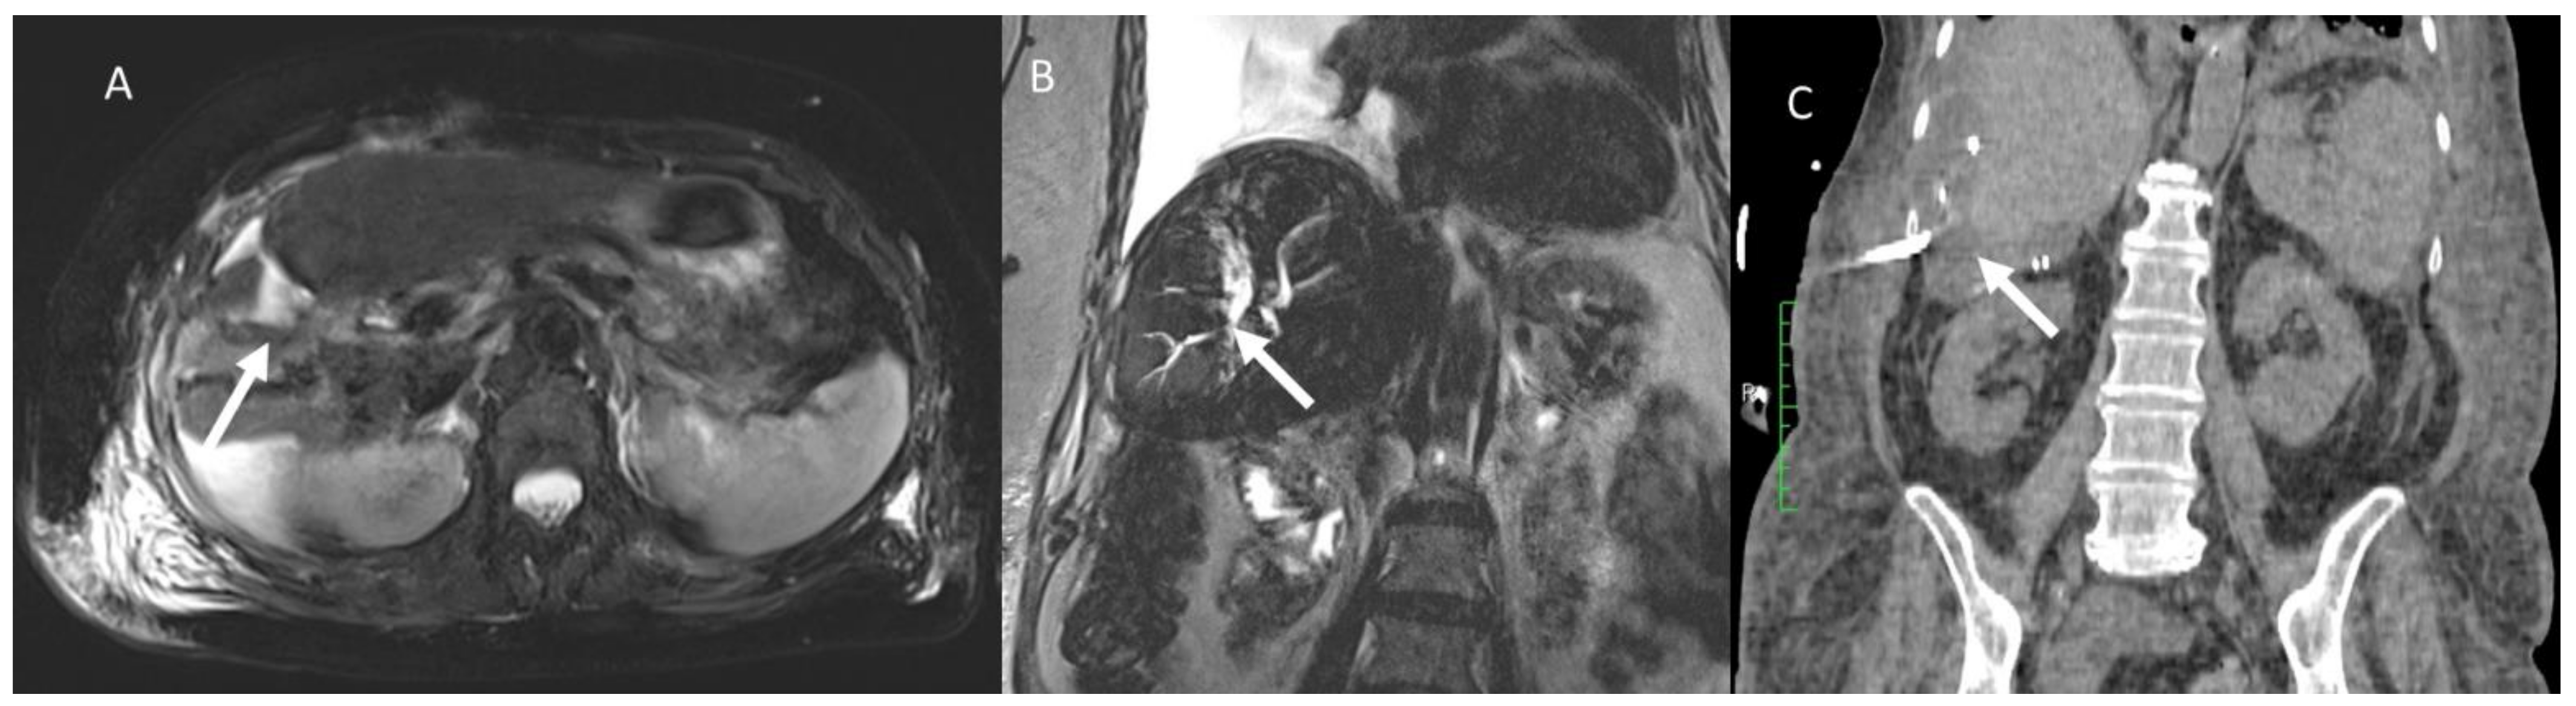

- Granata, V.; Grassi, R.; Fusco, R.; Setola, S.; Belli, A.; Piccirillo, M.; Pradella, S.; Giordano, M.; Cappabianca, S.; Brunese, L.; et al. Abbreviated MRI Protocol for the Assessment of Ablated Area in HCC Patients. Int. J. Environ. Res. Public Health 2021, 18, 3598. [Google Scholar] [CrossRef]